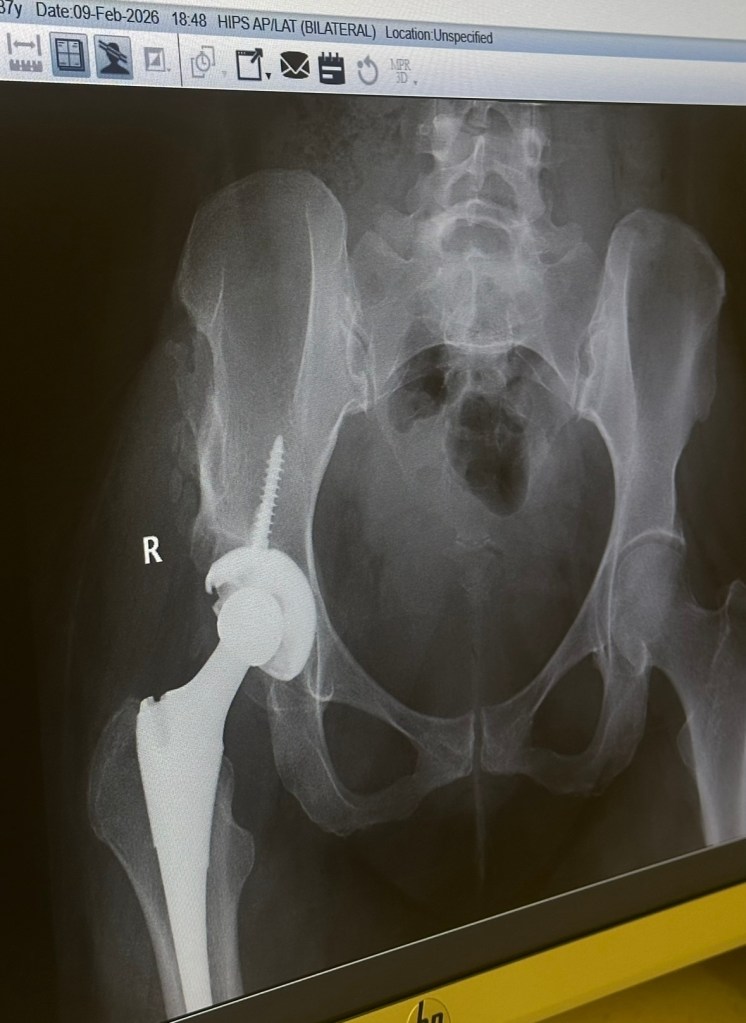

لكن عالم المال وتوسعه ودخوله كافة المجالات، غير شكل الطب، صناع الأدوية اعتبرونا سلعتهم الأساسية وحاربوا بعضهم من خلالنا ومؤخرا شركات التأمين الصحي، التي تأخذ أموالا طائلة تحت مسمى ” فئات التأمين ” وبعد ذلك تضع أطباء يقيمون طلبات العملاء من خلال شاشة وتقارير وترفض أو تقترح خطط بديلة وفق مصالحهم أو تعاقداتهم على حساب المستفيد. هذا الموضوع هو ما دفعني لكتابة المقال وعن تجربة أجدها غير منطقية أبدا، فأنا مشتركة مع شركة تأمين معينة وبفئة عالية تصل تغطيتها لملايين تحت بعض البنود، ترفض طلبات علاجي الأساسي لأن الطبيب الذي يصدر الموافقات يرى شيء مختلف عن طبيبي الذي يعالجني من أعوام ويعرف فعلا ما الذي أحتاجه وما المناسب لي! أي منطق هذا؟

قبل دخول شركات التأمين للمجال الطبي كنا نعالج إما في مستشفيات الحكومة أو المستشفيات الخاصة كل حسب قدرته وحتى في المستشفيات الخاصة كان العلاج يمشي وفق الاجراءات الطبية التي يحددها طبيب الحالة، أما الآن أطباء شركات التأمين هم من يحدد كيف نتعالج وما المرفوض وما المقبول دون أن يفحصونا بأنفسهم والتأكد من التاريخ المرضي، لأن كل شيء يبدأ من تاريخ التعاقد وليس تاريخ المريض فأي منطق هذا! أرجو وأطالب هيئة التأمين التدخل وفرض سياسات جديدة تصب في صالح المستفيد ” المريض” قبل صالح شركة التأمين.